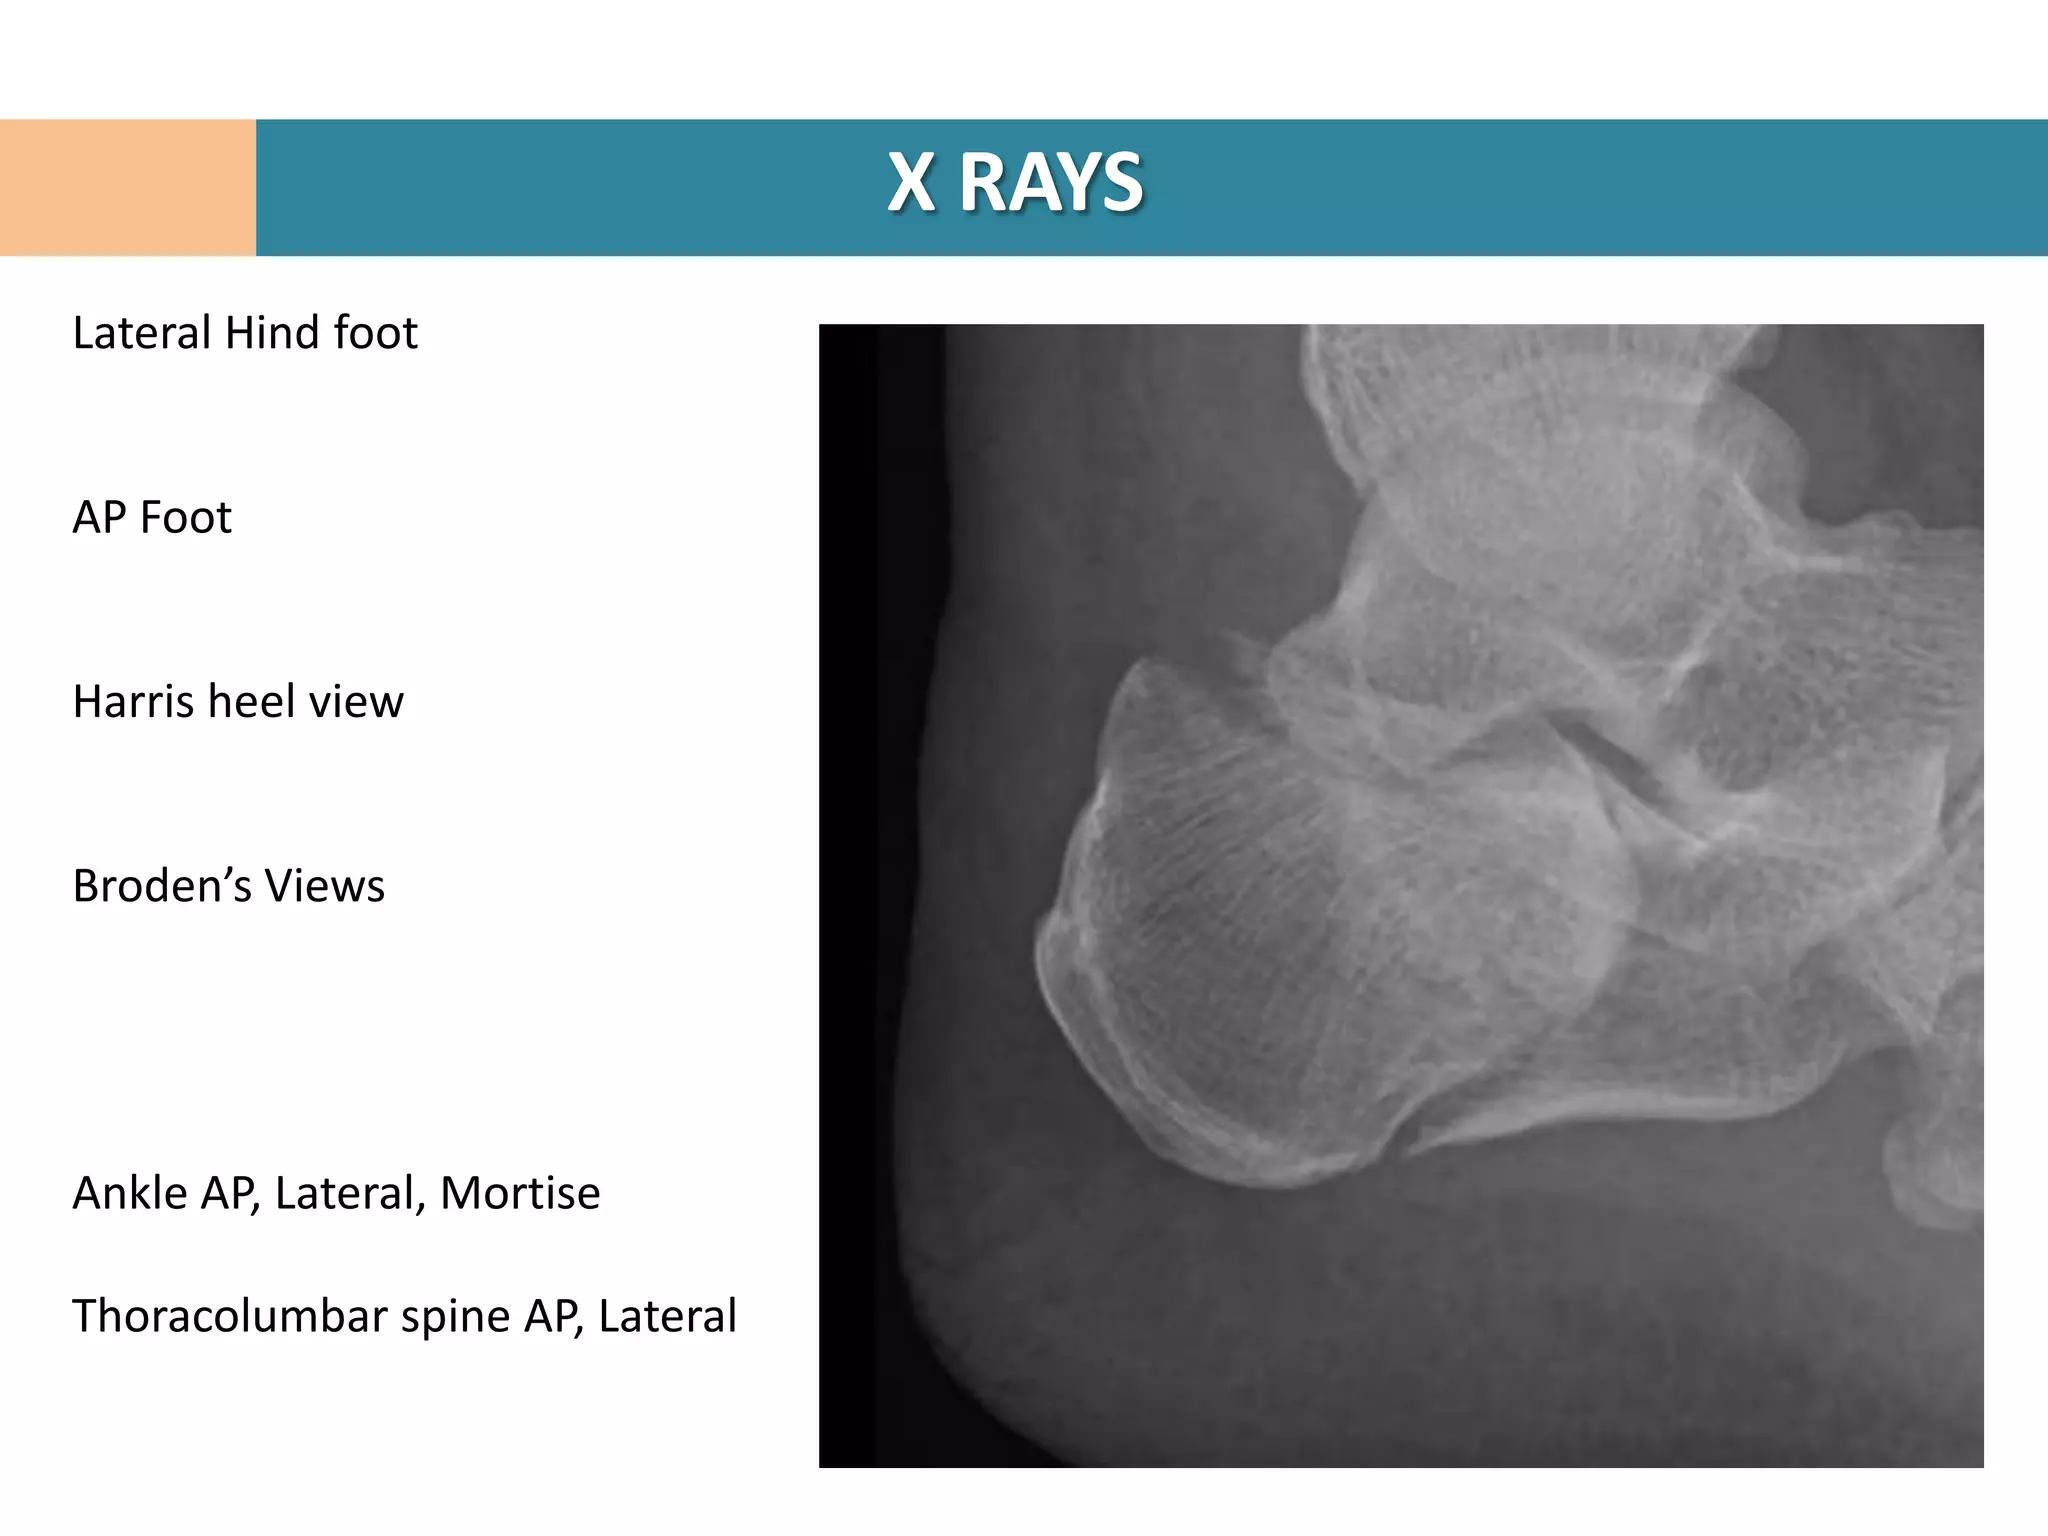

Lateral Hind foot

AP Foot

Harris heel view

Broden’s Views

Ankle AP, Lateral, Mortise

Thoracolumbar spine AP, Lateral